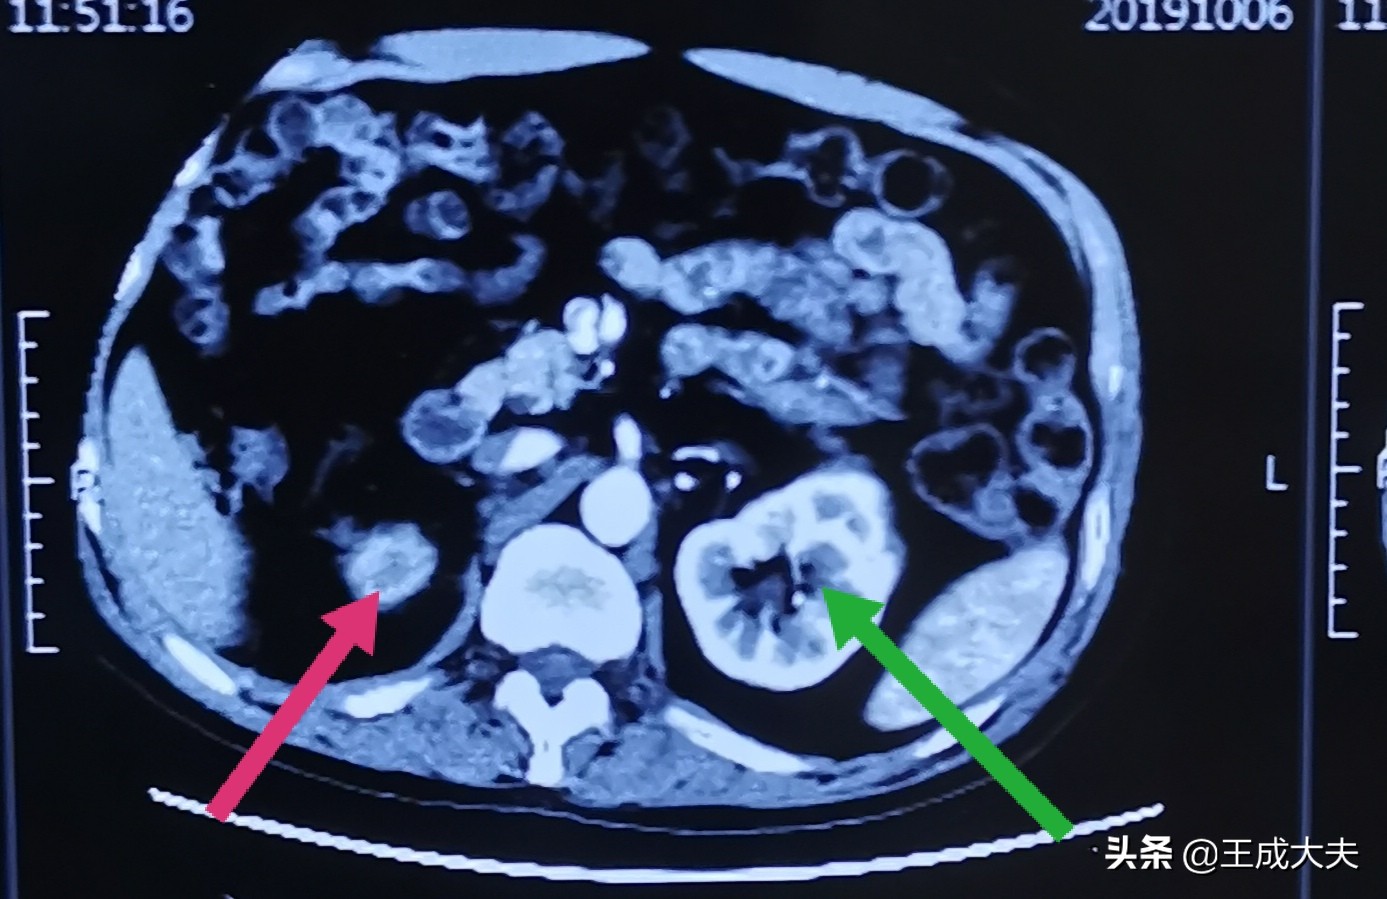

就在几天前,因出现血尿,这才又想起检查,

做CT提示:右侧输尿管结石仍然存在,右肾已经萎缩!

红色箭头所指右肾萎缩,绿色箭头所指左肾正常

做肾动态显像提示:右肾GFR6.1ml/min,基本没有功能!(注:GFR<10ml/min,有切肾指征)

原来,患者输尿管结石堵塞尿路后,尿液流出障碍,右侧肾脏出现积水,压迫正常右肾组织,破坏肾单位,随着时间的延续,残留的肾单位越来越少,最终右肾丧失功能,萎缩成一团。